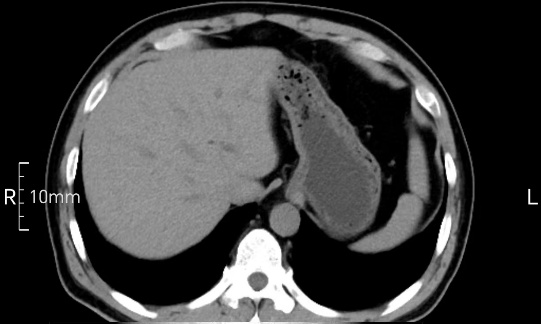

看看下面三幅便知遵醫(yī)囑的重要性。

禁食但檢查前沒有喝飽,胃未能漲開,胃壁觀察效果不佳。